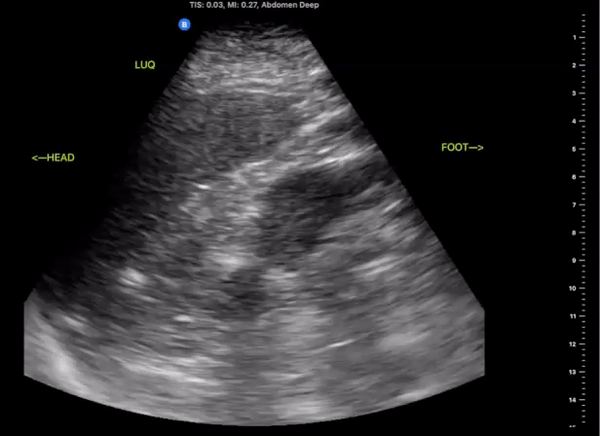

Left Upper Quadrant

(LUQ)

Probe/Preset:

Curvilinear, Phased Array/ FAST, Abdominal

Body Plane:

Coronal

Probe Indicator:

Towards Head

Depth:

At least 15cm

Location:

Posterior Axillary line the level of the xiphoid

Identify:

-

Left Kidney

Diaphragm

Spleen

Notes:

Scan through the area assessing the around the spleen, splenorenal space, and inferior pole of the kidney